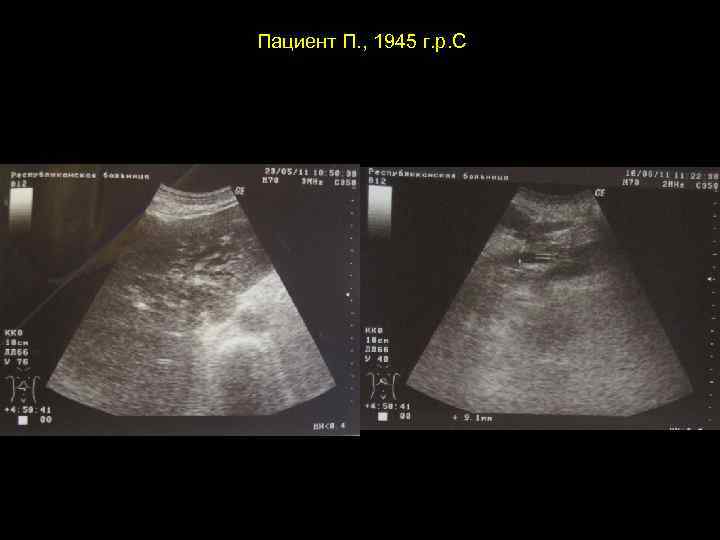

Пациент П. , 1945 г. р. С

Тот же пациент